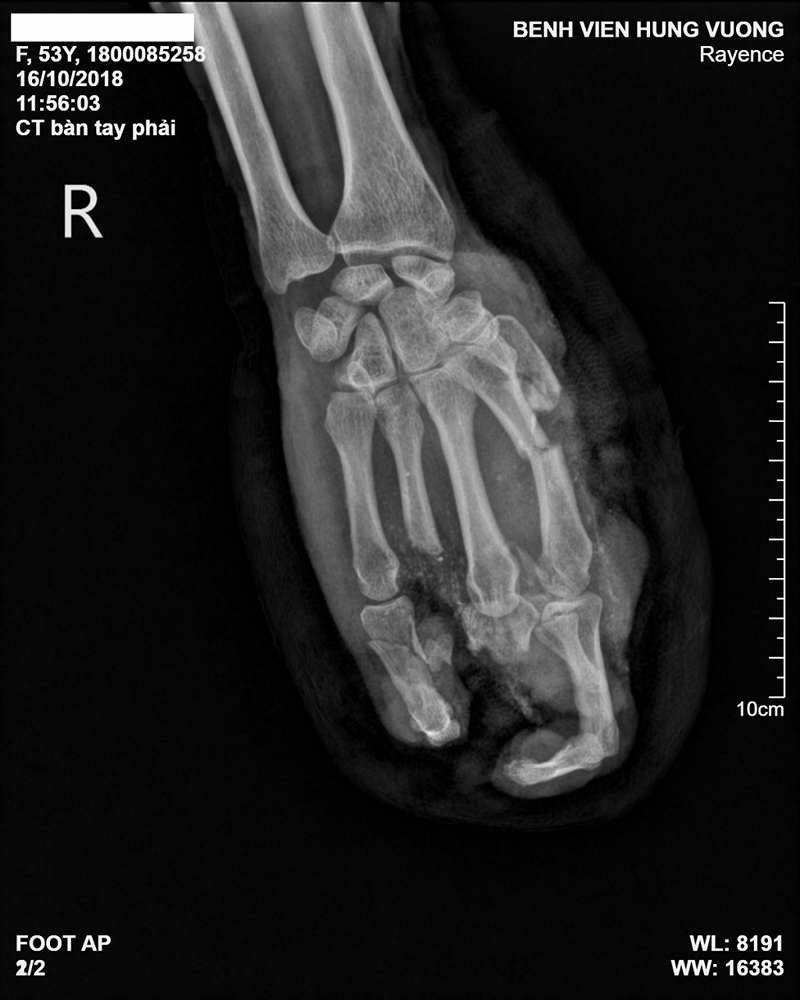

Ngày 17/10, thông tin từ bệnh viện đa khoa (BVĐK) Hùng Vương, Yên Bái, cho biết nơi đây vừa tiếp nhận bệnh nhân LTD, 53 tuổi, quê Yên Bái nhập viện trong tình trạng bàn tay phải dập nát nham nhở, chảy nhiều máu, hai ngón bị đứt rời.

Ngay lập tức bệnh nhân được vệ sinh vết thương và cầm máu. Kết quả chụp X-quang bàn tay phải cho thấy bệnh nhân bị gãy cụt phức tạp các xương bàn, ngón tay phải.

Ảnh chụp X-quang bàn tay của bệnh nhân. |

Theo như người nhà bệnh nhân kể lại, bệnh nhân là công nhân làm việc tại một xưởng làm gạch bê tông. Do sơ xuất trong quá trình làm việc nên bị máy ép gạch nghiền vào tay. Máy có công suất rất lớn và nhanh nên không kịp cứu vãn. Sau khi bị tai nạn bệnh nhân được chuyển ngay đến BV cấp cứu.